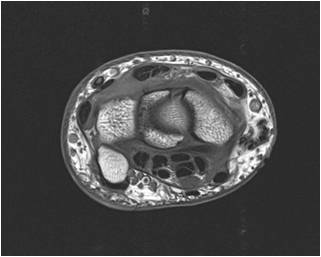

Wrist and Carpal Tunnel

Identify: Median nerve, flexor pollicis longus, pisiform, scaphoid, flexor carpi radialis, extensor pollicis brevis, extensor pollicis longus, radial artery, palmaris longus, ulnar artery, triquetrum.